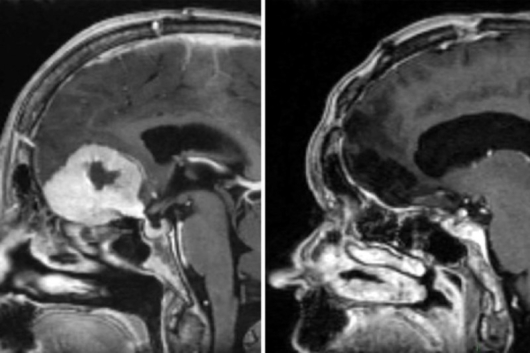

Хирург, работещ в Шотландия, разработи начин за отстраняване на мозъчен тумор с размер на ябълка през веждата на пациент, което се смята за първата подобна процедура в света.

Адаптирана техника Неврохирургът Anastasios Jamouriadis от NHS Grampian Health Service е адаптирал съществуваща лапароскопска техника за отстраняване на тумори, която оставя значително по-малко белези от конвенционалната краниотомия.

Промяната позволява на Джамурадис да отстрани много по-големи тумори от предната част на мозъка, отколкото преди, като някои от тях са с размерите на голяма ябълка.